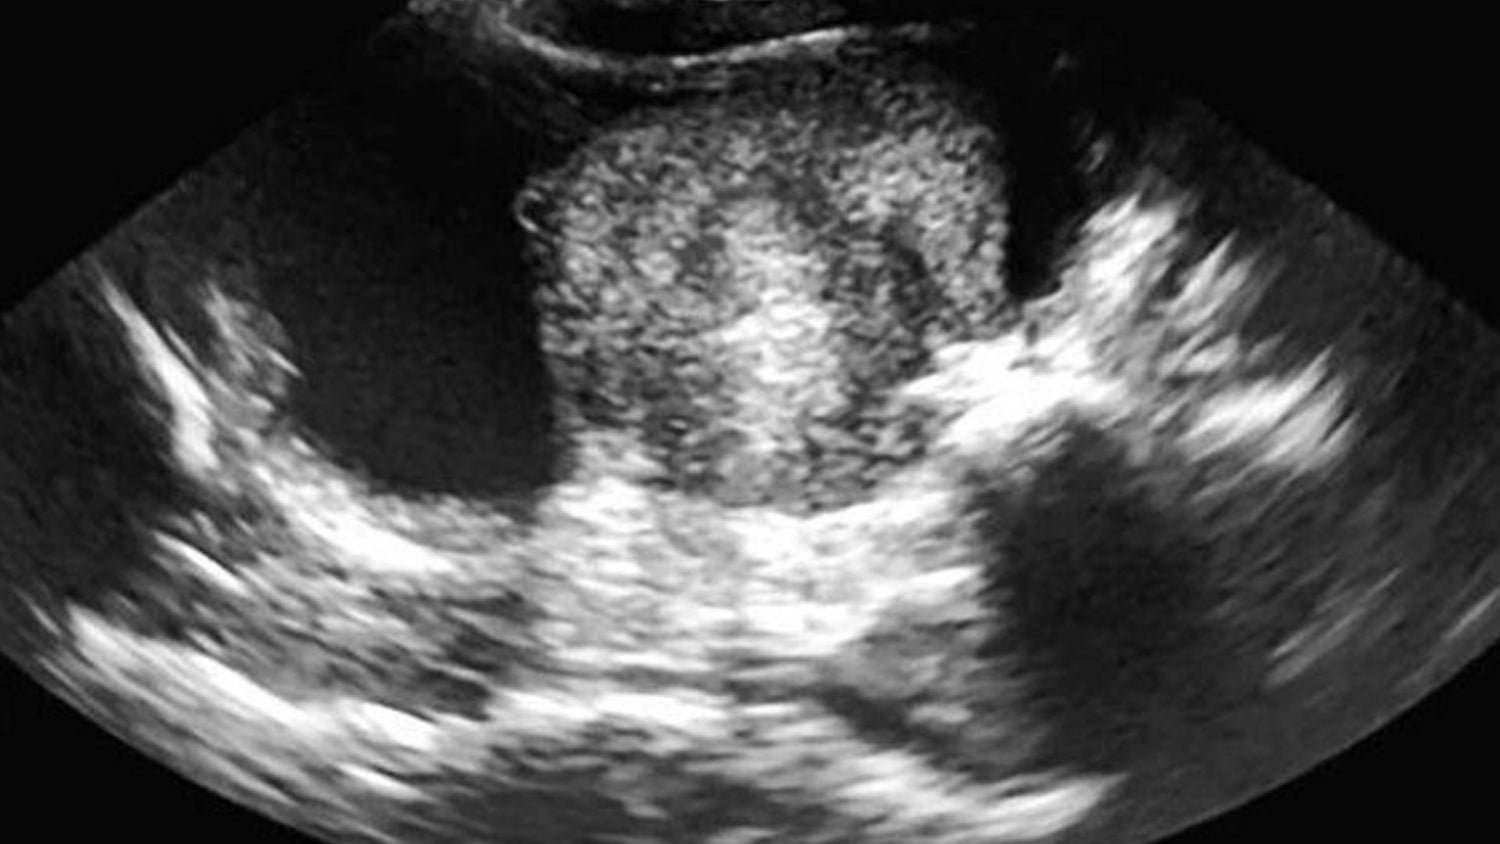

Ecografía

Utilizamos ecografía veterinaria para diagnosticar y monitorear la salud interna de tu mascota de forma segura y no invasiva. Este estudio nos permite evaluar órganos, detectar gestaciones, identificar anomalías y dar un diagnóstico preciso para un tratamiento oportuno.